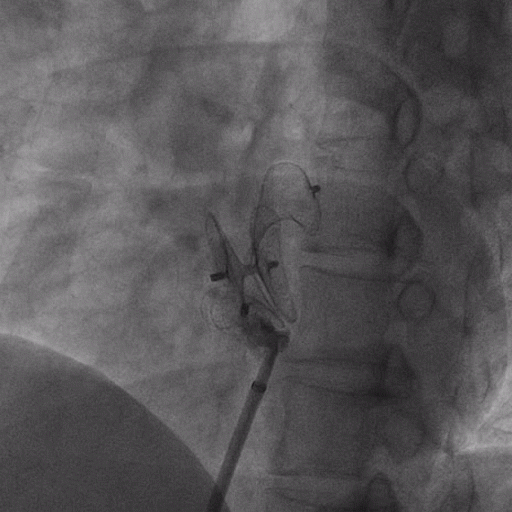

在獲得患者同意后,1月12日,尚福軍主任為患者進(jìn)行了PFO封堵術(shù)。術(shù)中造影可見封堵器殘余漏,尚福軍主任用精湛的技藝,順利通過封堵器殘余漏裂縫,將右心導(dǎo)管從右房送入左房,且順利到達(dá)肺靜脈;遂行卵圓孔未閉封堵術(shù)后殘余漏再次封堵;且完美釋放PFO封堵器,可見兩封堵器呈“馬蹄蓮”狀,再次術(shù)中造影未見殘余漏。